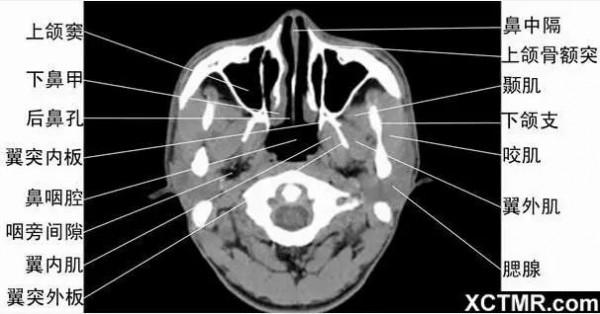

頭頸五官CT斷層解剖圖及常見病影像診斷

頭頸五官CT斷層解剖圖